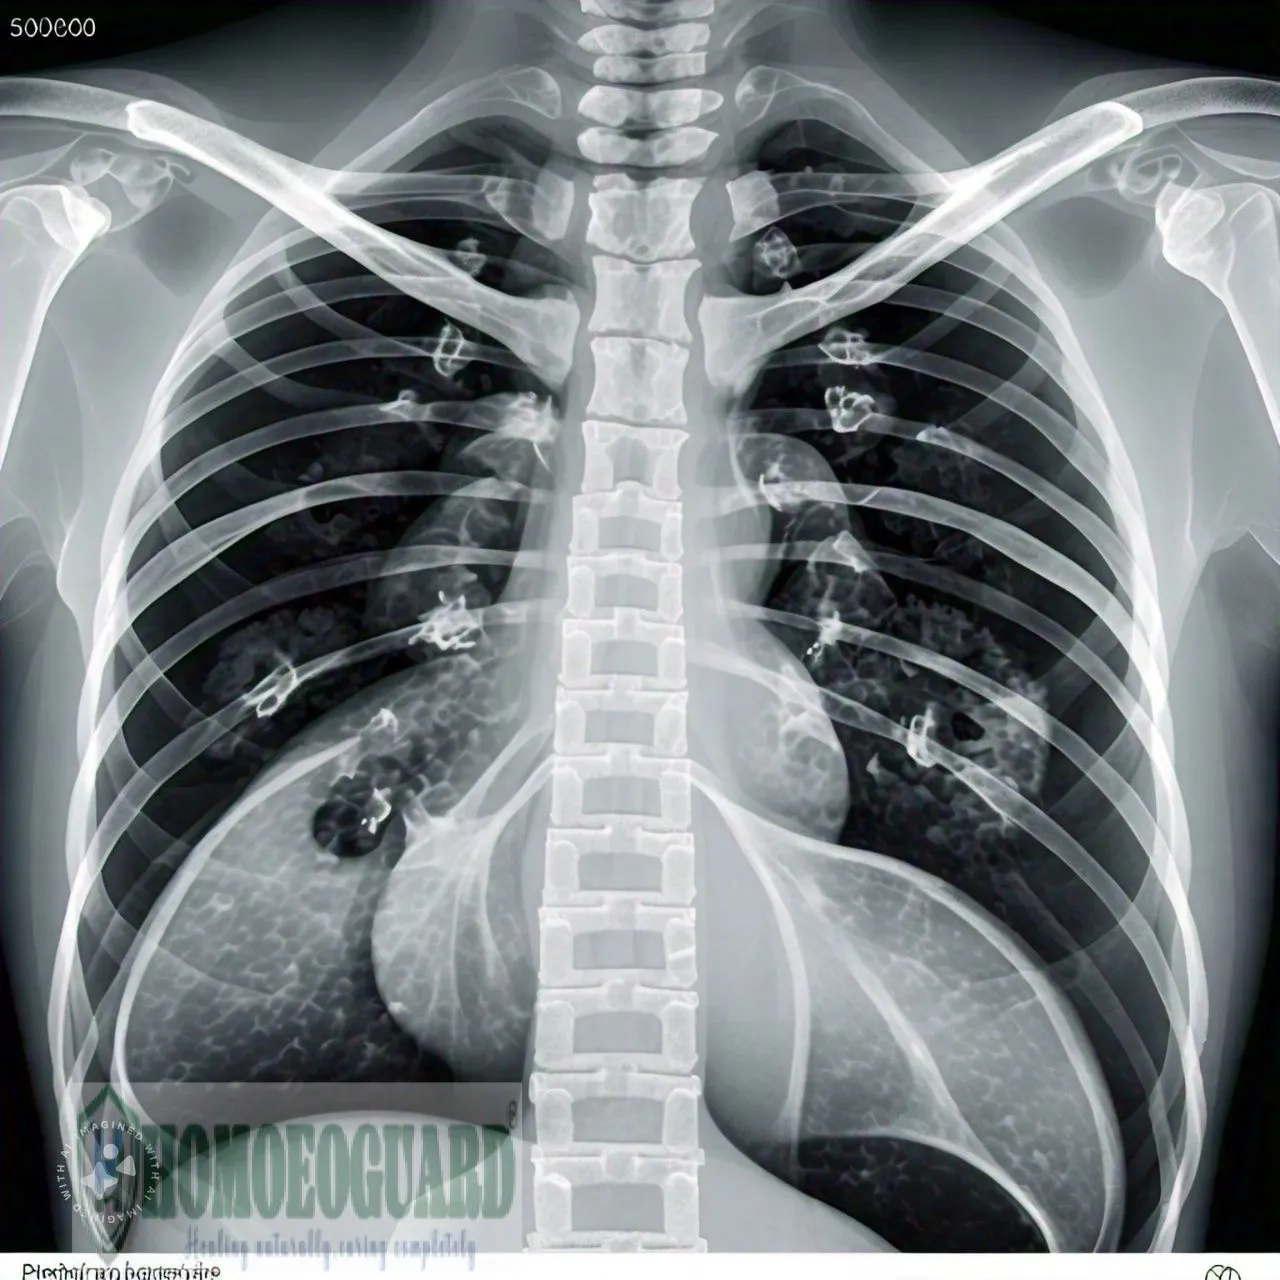

Pneumonia | HomoeoGuard

Understanding Pneumonia

Pneumonia is an infection that inflames the air sacs in one or both lungs. It can be caused by various organisms, including bacteria, viruses, and fungi. Pneumonia can range in seriousness from mild to life-threatening, especially in older adults, infants, and individuals with weakened immune systems.